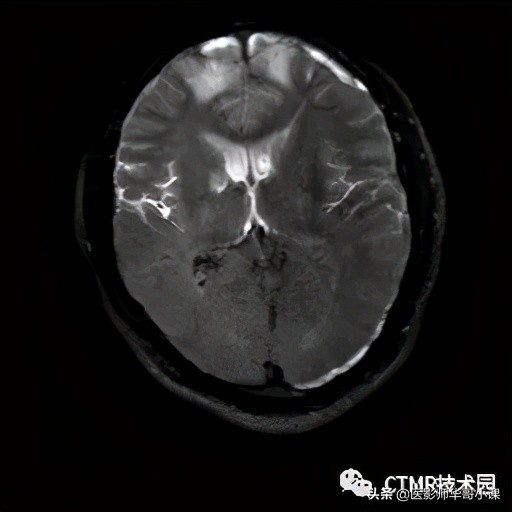

为什么想要去分析这个序列呢,是因为在一次值班中,遇到一个神经外科的病人,颅内有挫裂伤出血,神志有点不清楚,似是可以交流,但还是不配合,检查过程中还是无意识地乱动。听家属和陪同来的护工说,已经来了好几次了,都是因为躁动没做成而回去了。扫了下弥散,看到颅内有好多挫裂伤出血灶。遇到这样的病人,我通常都用机器自带的单次激发序列来试试,其中就有一个序列就是 SSh_FLAIR,用来扫压水。那么扫的效果怎么样呢?(总共18层 6mm/1mm,只显示部分)

由于这个病人一个劲乱动,还时不时地抬头,我们可以看到,扫出的图像感觉不是很连续,或者说相邻两幅图像之间有重复的部分。还可以看到第三行第二列的图像有部分脑脊液没有被抑制完全,而且可以看到前后两图比起来它的位置有所变化,即病人抬头了:

由序列的研究可知,是先施加 180° 反转脉冲,等待 TI 时间再进行信号采集。那么由于运动,就产生了部分被反转,部分未被反转。以后面的被反转为基准来看,那么前面的就是未被反转,由于病人运动的维度不只是 2D 平面内晃动,而是 3D 空间的乱动,抬头,扭动等。那么很容易导致脑脊液未被反转的空间组织进入成像范围,这将导致脑脊液呈高信号。正是由于施加 180° 反转脉冲时会动,采集图像时也会动,而且都是3D维度的运动,那么最终得到的图像的空间是两者的相交。

可以看到未被 180° 脉冲激发的组织进入了采集范围。当然这只是模式图,在扫描时病人的运动可能更复杂,我记得在后面的扫描过程中,病人都脱离线圈了,从线圈中滑出来了……